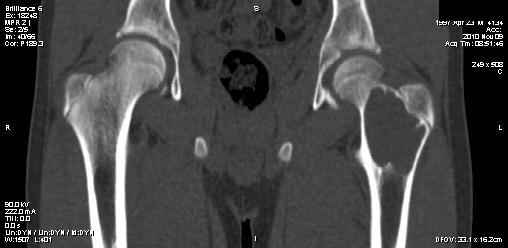

Киста шейки бедра

Мальчик 13 лет. В течение нескольких месяцев беспокоят боли в левом тазобедренном суставе.

При обследовании выявлена киста шейки левого бедра с сопутствующими изменениями в головке бедра, которые мы трактуем как дистрофические. Планируем вскрытие и санацию полости кисты передне-боковым доступом, костную пластику. Перед нами возникли следующие вопросы: для пластики использовать крыло подвздошной кости либо большеберцовую кость,либо их комбинацию, (полость большая,одним крылом можно не обойтись) или донорский аллотрансплантат с Коллапаном? Фиксировать ли? Если фиксировать, то чем? Доступны обычные угловые пластины либо АВФ.